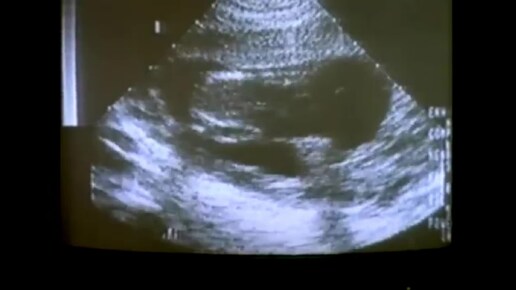

Детоубийство приобрело катастрофические масштабы. Радугамира.